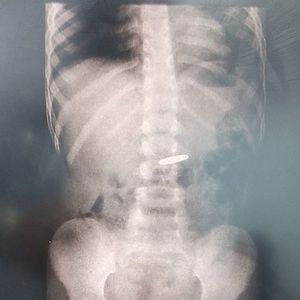

This X-Ray shows a coin swallowed by a little girl. The management of this case is observation as the coin will probably gets execreted within 3-4 days, the patient is advised to eat food rich in fibers such as wheat, corn, rice bran, macaroni, or even fruits and vegetables. If it is a large forigen body then it may obstruct the gastrointestinal tract and surgery is used to manage such cases.